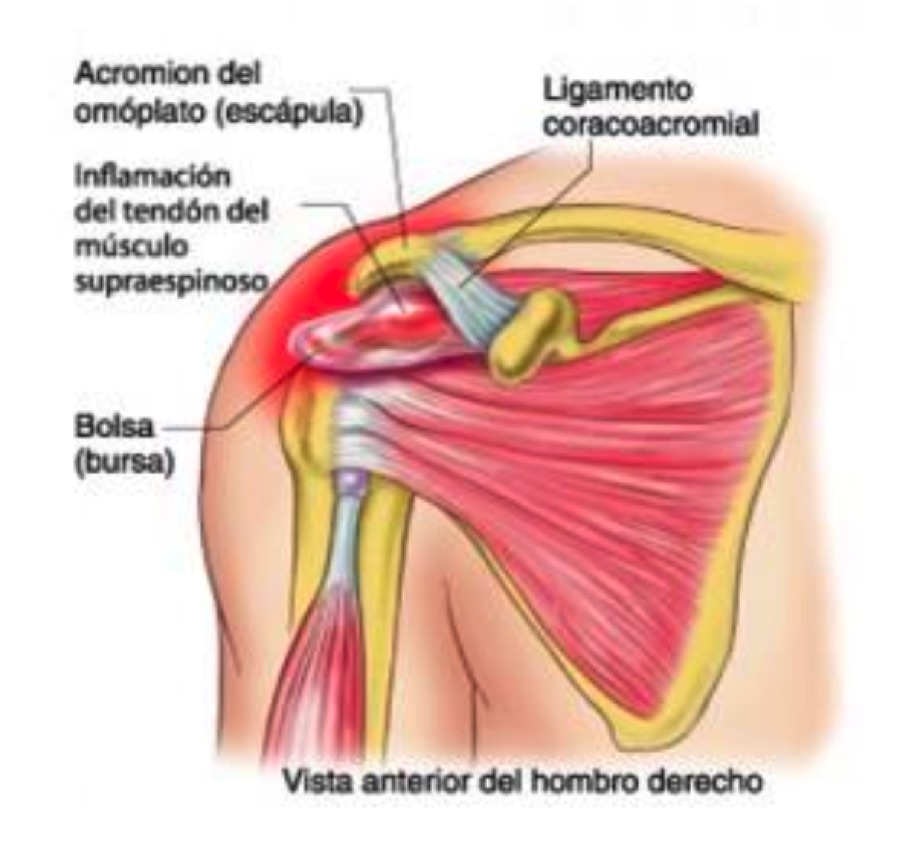

Фотографии мышц ротаторной манжеты плеча